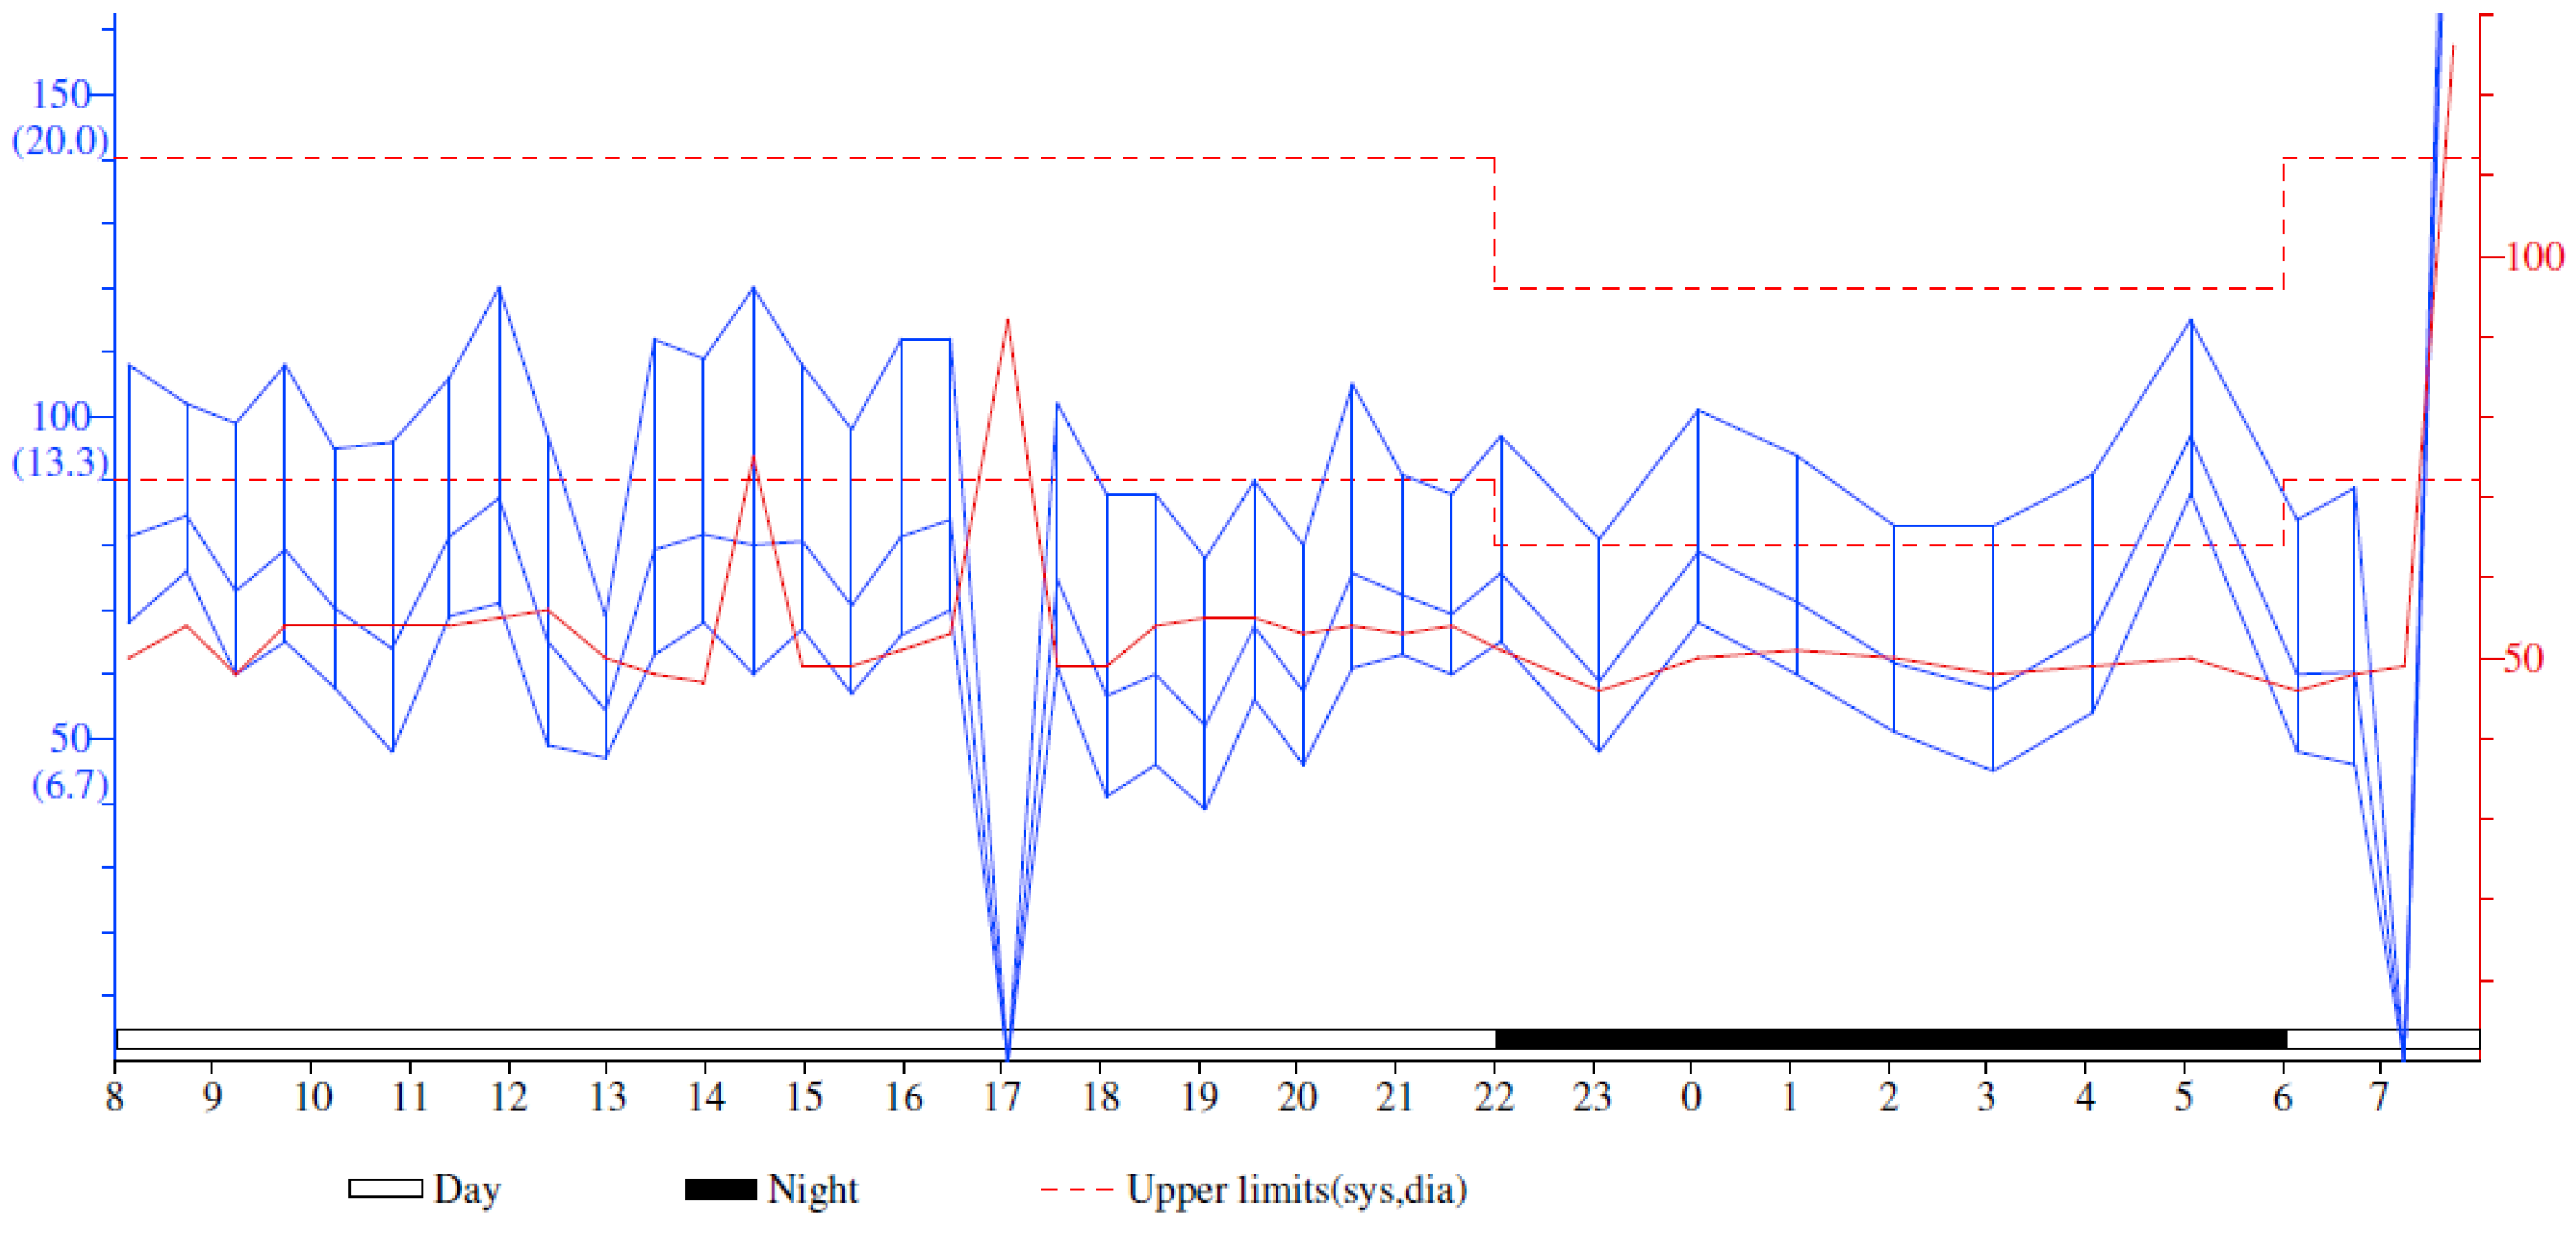

2. Detailed Case Description